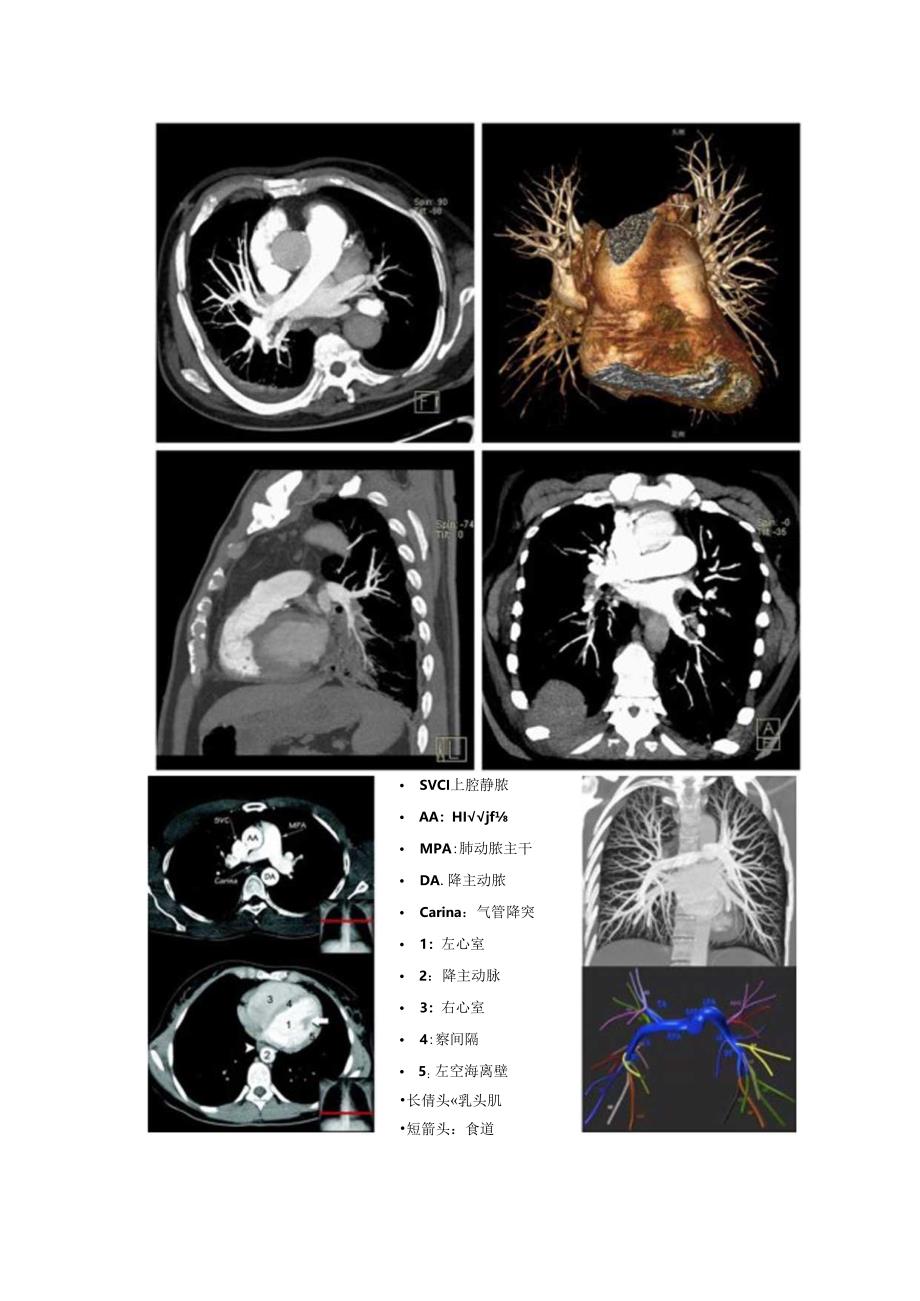

1、临床肺栓塞诊断策略、血管结构、急慢性肺栓塞CTPA征象存在伪影要点Cr肺动脉造影(CTPA)简便、无创,且敏感性和特异性都很高,是诊断肺栓塞的首选检查。指南推荐诊断策略解剖结构肺血管分支示意图右肺动脓干叶间动脉叶级动脉I级静豚段级动脓/静I*亚段级动脉/龄脉小叶级动脓/冷脉 SVCI上腔静脓 AA:HIjf MPA:肺动脓主干 DA.降主动脓 Carina:气管降突 1:左心室 2:降主动脉 3:右心室 4:察间隔 5:左空海离壁长倩头乳头肌短箭头:食道尖段动脓A1IW段动脉AJ左肺动脉上段动脉.%后底段A10卜舌段A.尖后段动脉Ay后段动脓Al中叶动脉/内侧段外侧段AJ前底段AME外储底段A